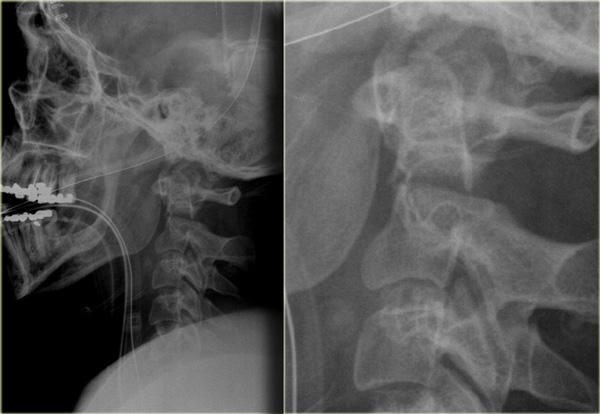

Bên trái là hình ảnh của một phụ nữ 44 tuổi bị ngã trên băng.

Sau đó bà bị ngã lần thứ hai vào sáng hôm sau, và sau đó mất hoàn toàn vận động và cảm giác.

Khám thực thể cho thấy liệt hai chi dưới kèm yếu nhẹ chi trên bên phải.

Ban đầu được đề xuất chẩn đoán tổn thương tủy trung tâm.

X-quang bình thường.

Các dấu hiệu bao gồm:

- Các mảnh xương nhỏ tách ra từ mặt khớp trên và dưới

- Khoang gian gai rộng ra tại C5-6

- Sưng nề mô mềm ở mức này về phía sau

- Hẹp nhẹ khoang đĩa đệm tại mức C5-6.

Các dấu hiệu CT này rất tinh tế và dường như không tương xứng với vấn đề thần kinh.

Trong trường hợp như vậy, MRI là bước tiếp theo cần thực hiện.

Đầu tiên chúng tôi trình bày hình CT mặt phẳng coronal và axial với cửa sổ mô mềm.

Có vật liệu tăng tỷ trọng ở phía sau khoang đĩa đệm, rất gợi ý thoát vị đĩa đệm do chấn thương.

Tụ máu ngoài màng cứng cần được đưa vào chẩn đoán phân biệt, nhưng dấu hiệu này chỉ giới hạn ở vùng khoang đĩa đệm, khác với hình ảnh của khối máu tụ.